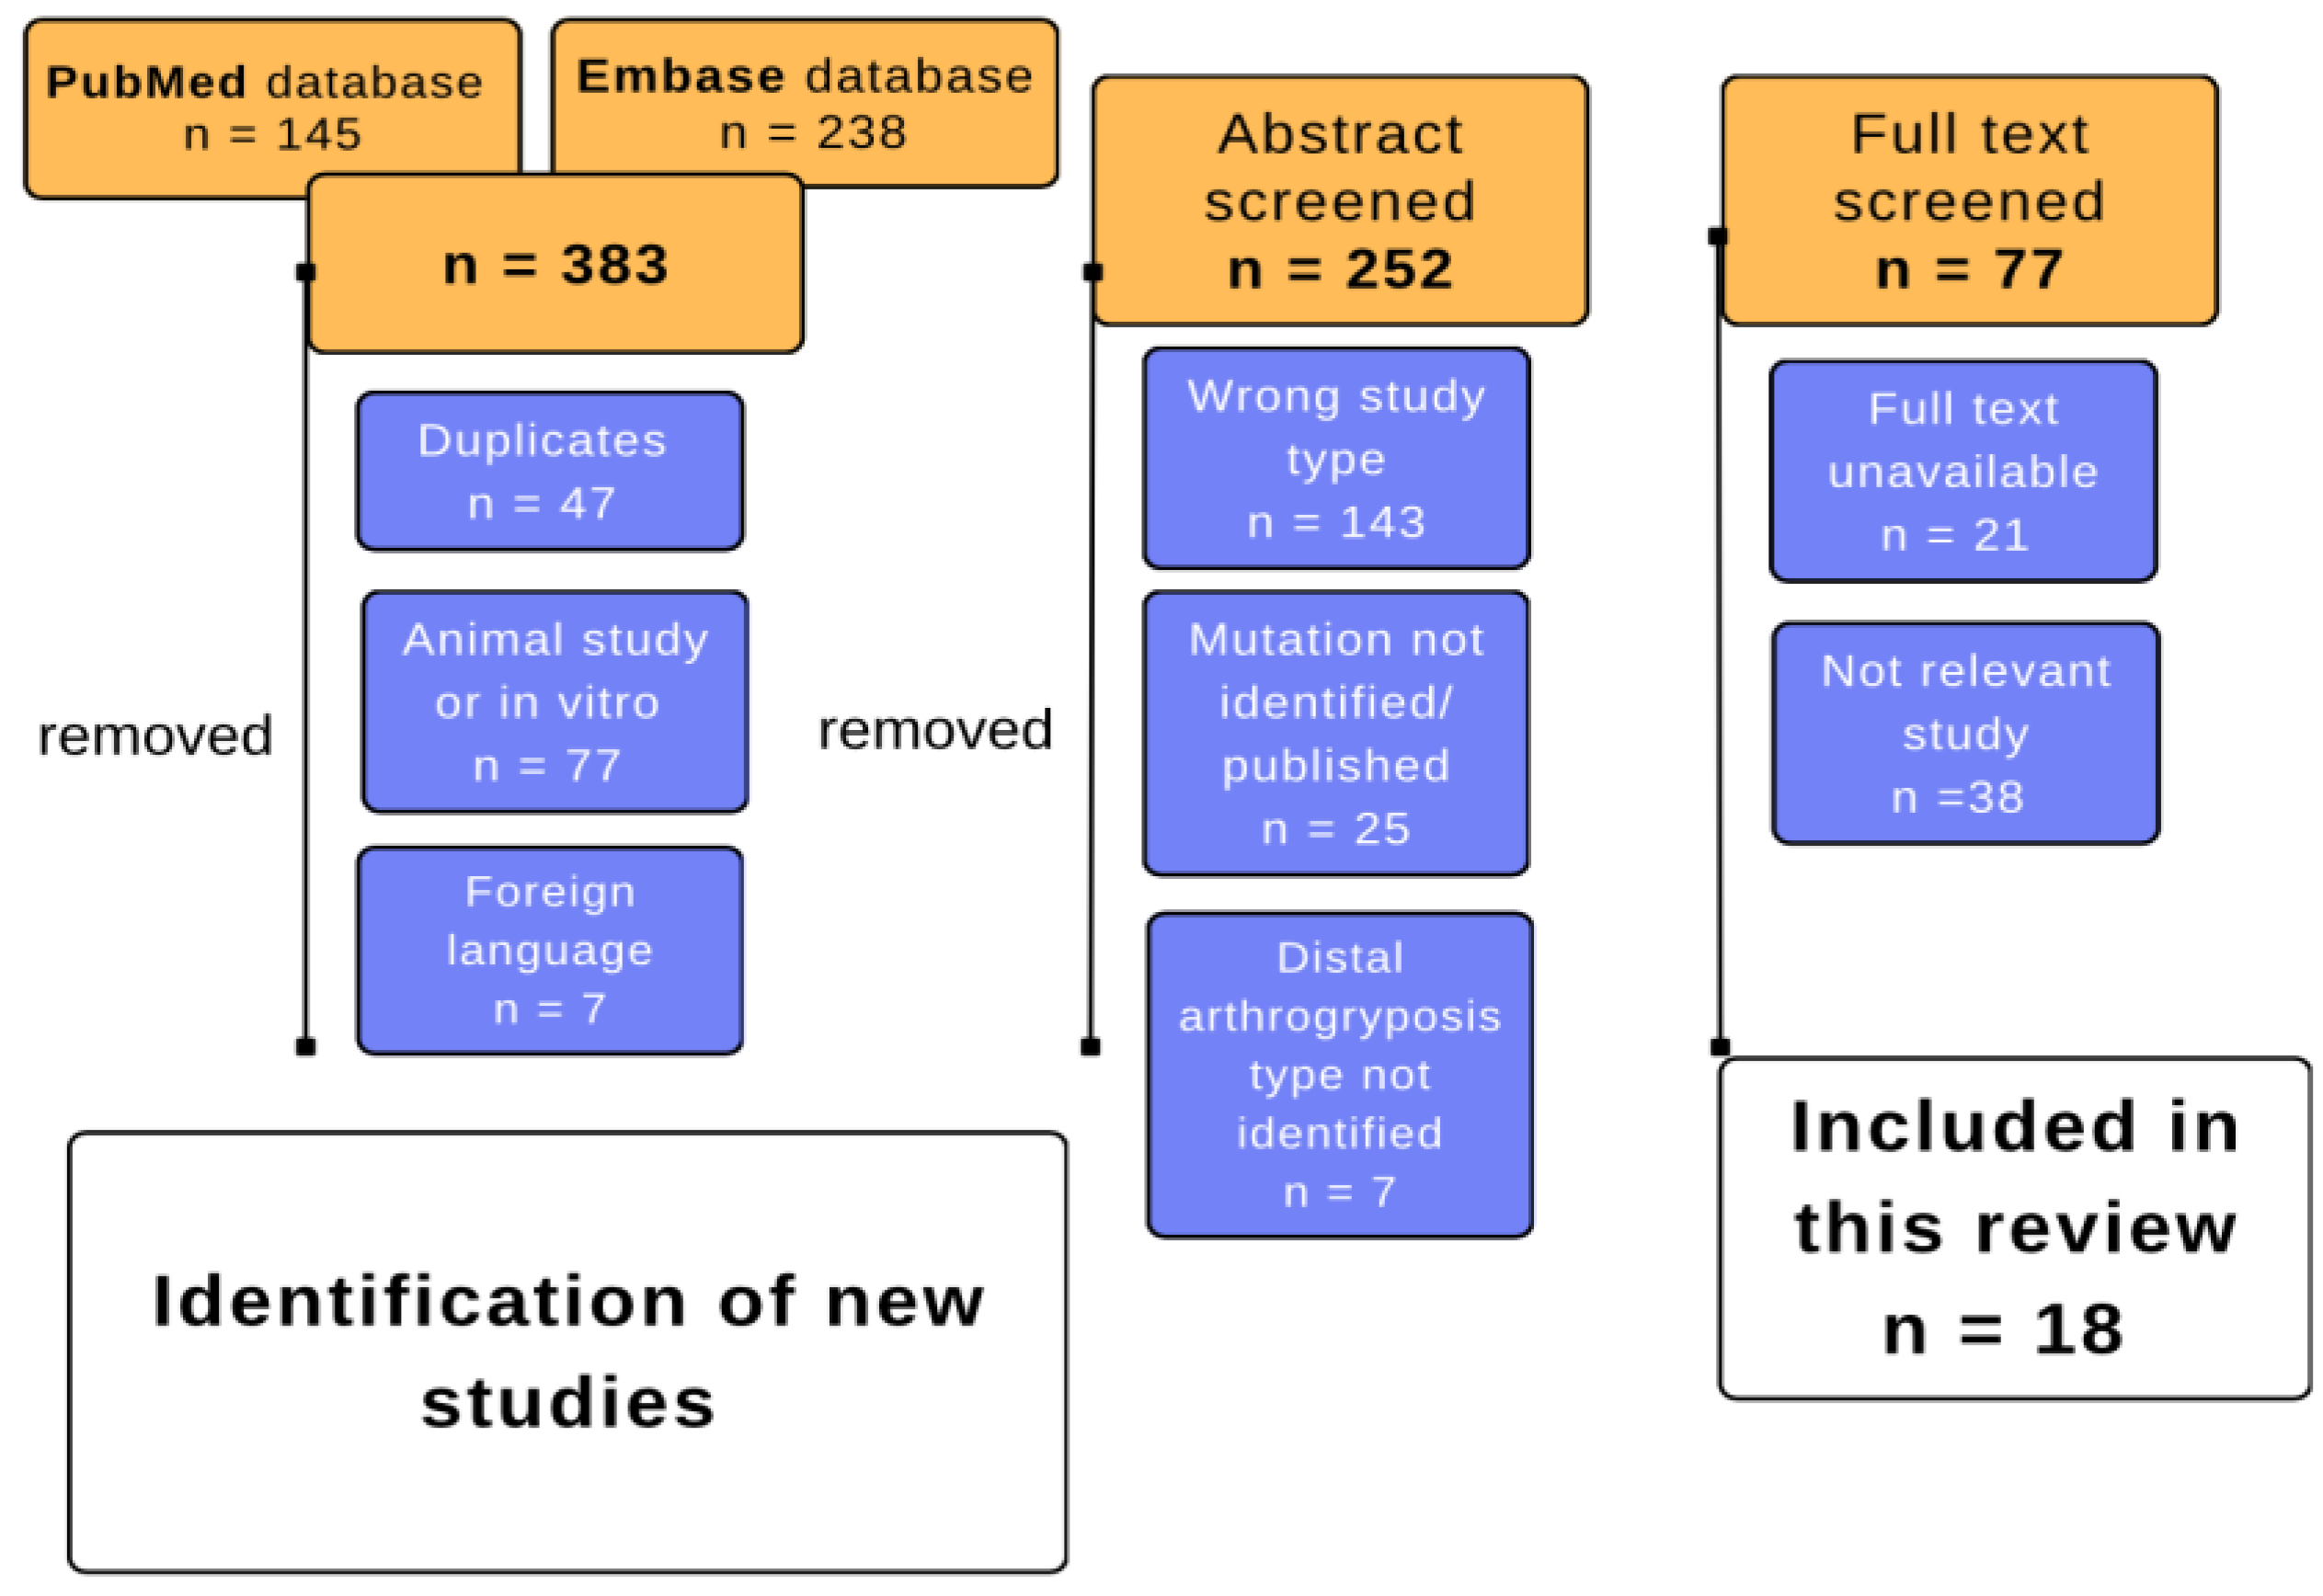

2. Materials and Methods

3. Results